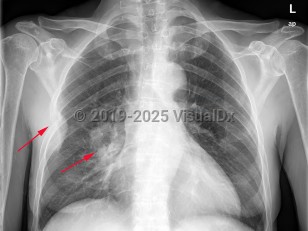

Pneumothorax

Spontaneous pneumothoraxSpontaneous pneumothorax